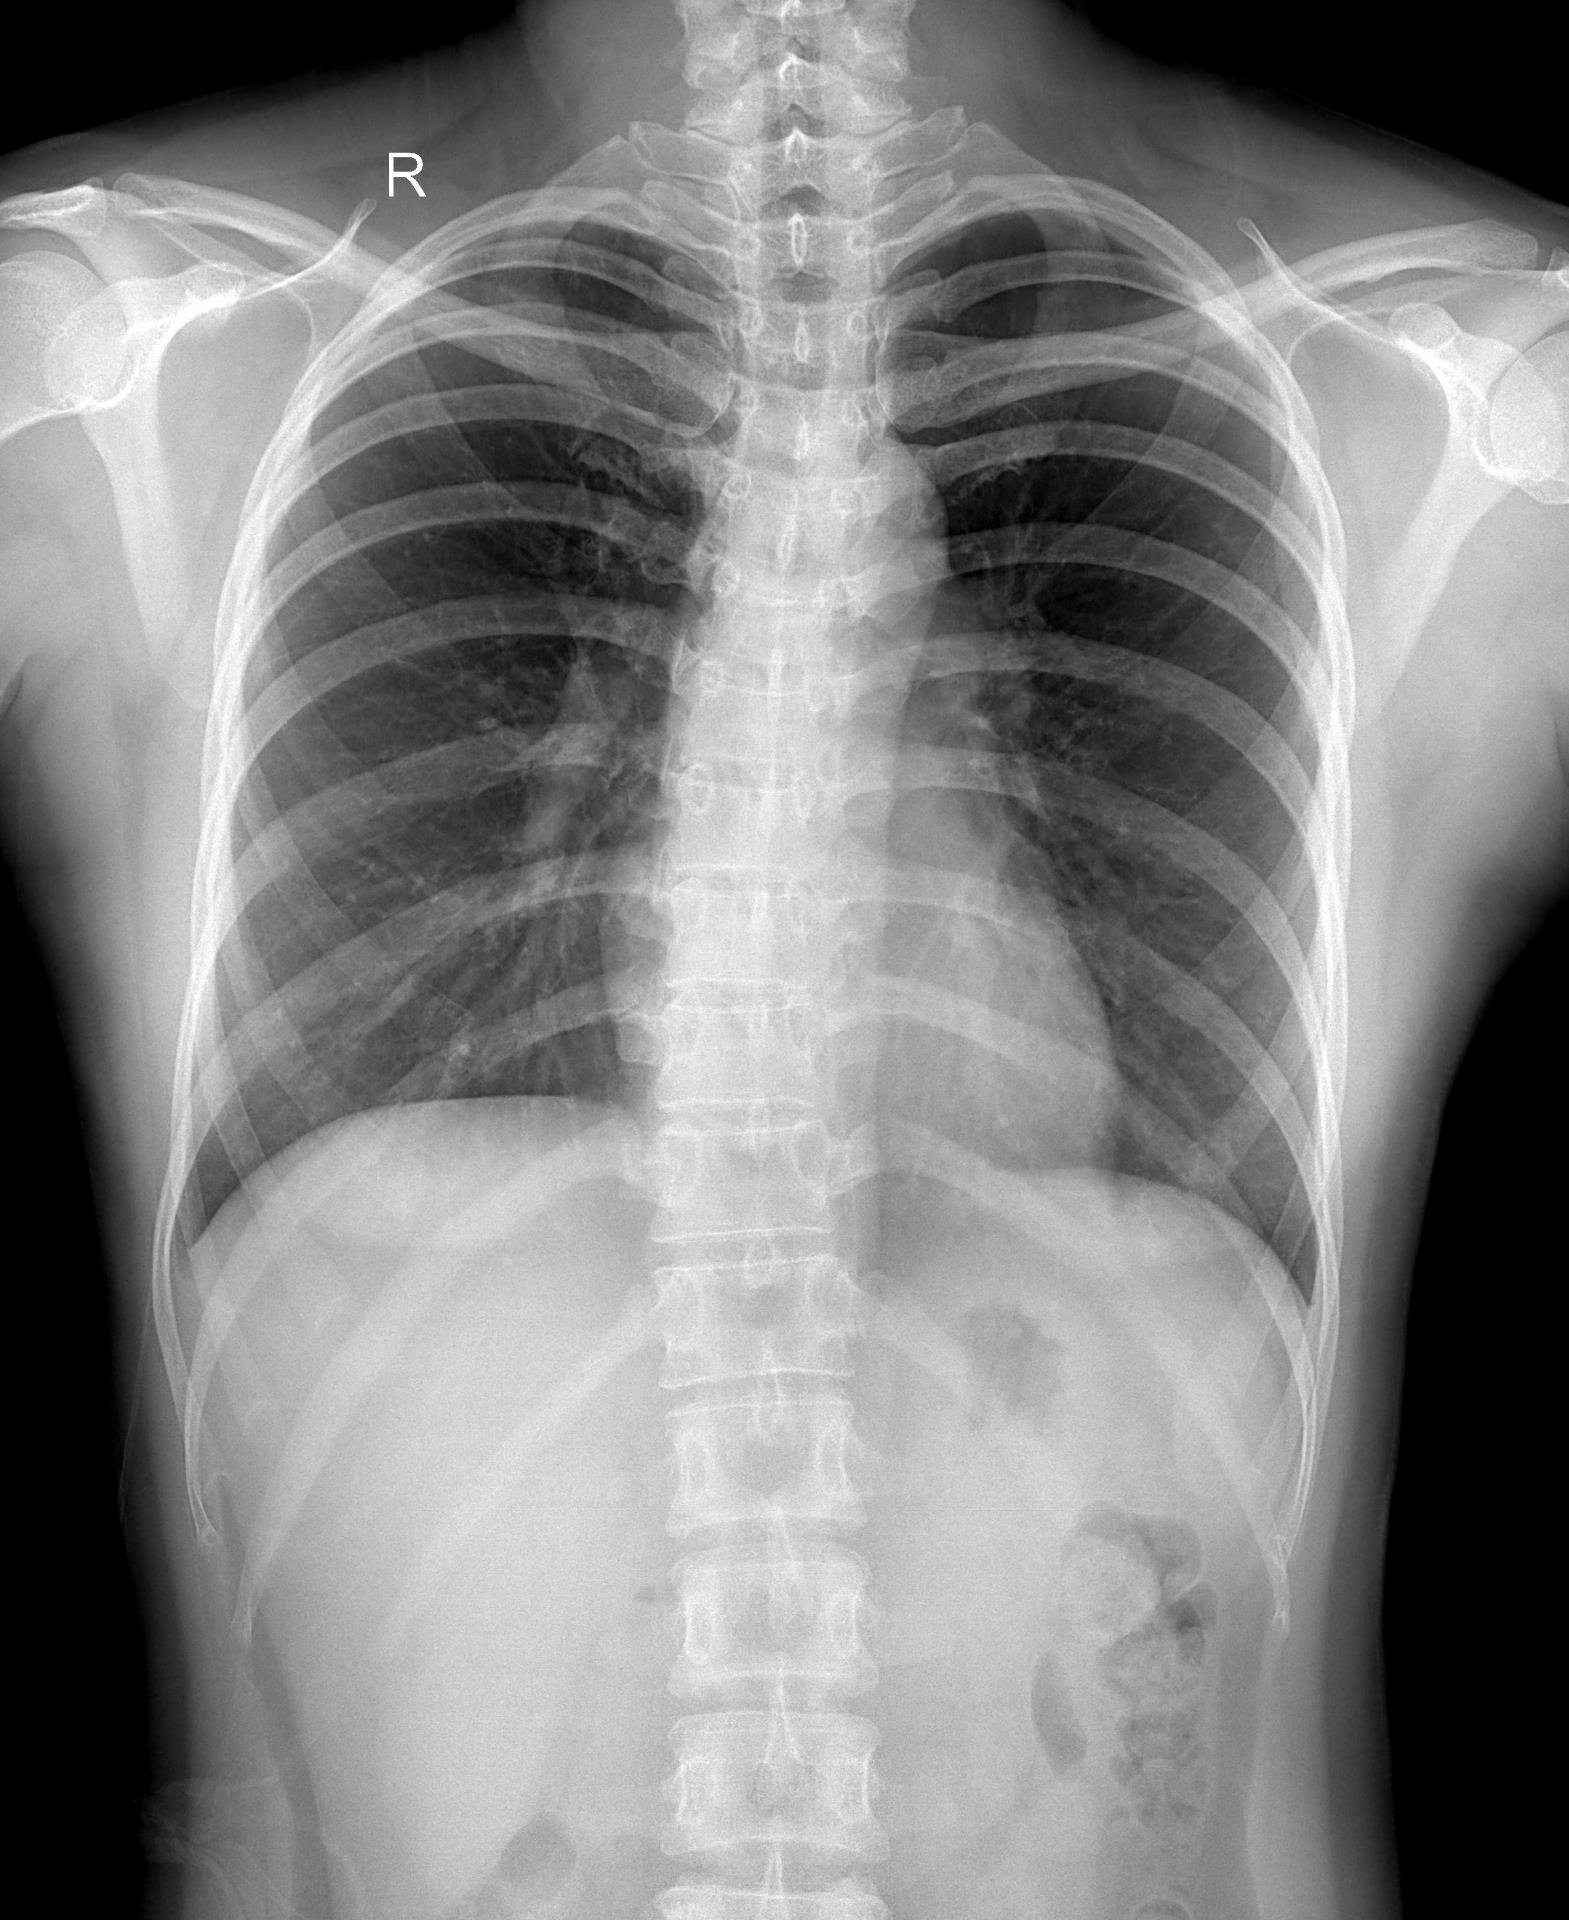

Hệ thống máy X-quang hiện đại, cho hình ảnh rõ nét, liều tia được kiểm soát an toàn.

DHA Healthcare với hệ thống máy móc hiện đại, cho hình ảnh rõ nét, tia liều được đảm bảo.

Tại Phòng khám Đa khoa DHA Healthcare, dịch vụ chụp X-quang cột sống được thực hiện với: